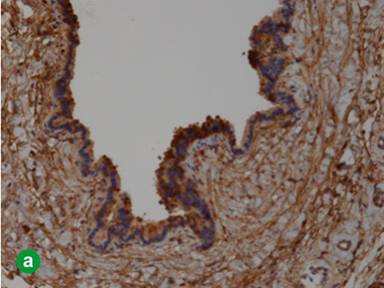

The cystic lining cells were focally reactive to CK7 and Trypsin (Figure 6a) but negative for calretinin, WT1, PAX8, CD31, and CK20. The luminal border of the epithelium was also reactive to EMA. Histochemical staining for PAS was negative in the epithelium. The residual pancreatic islet could be highlighted by IHC stain for synaptophysin (Figure 6b). The whole picture was more like a rare acinar cell cystadenoma.

|

Figure 6. a. The lining cells were reactive to Trypsin. b. The residual islets of Langerhans (arrow) were positive for synaptophysin, but the lining epithelium was negative. |